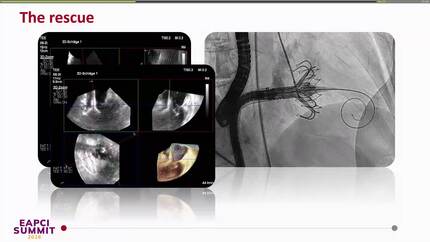

Rescue TTVR with a new-sized EVOQUE valve following transcatheter edge-to-edge repair